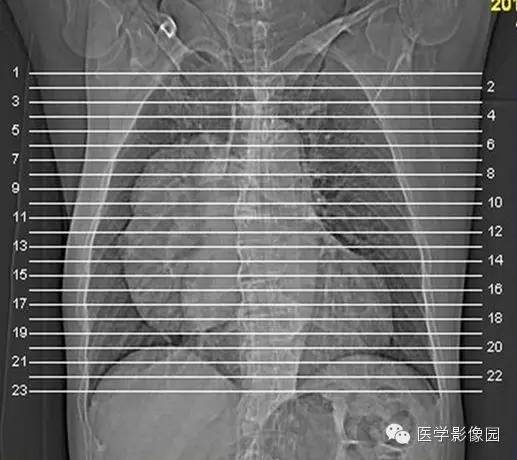

纵隔占位?肺内占位?巨大中央型肺癌1例

【病例】巨大中央型肺癌1例